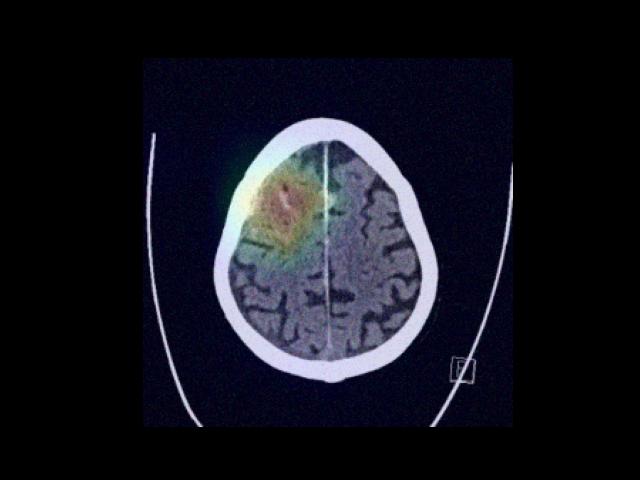

Sample Gallery